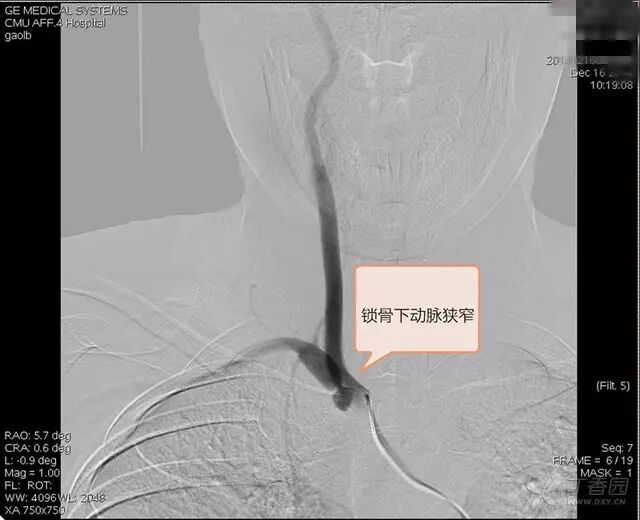

DSA:右锁骨下动脉起始部狭窄,狭窄率 96%,右椎动脉血流前向,右胚胎性大脑后动脉,左颈总动脉闭塞,左后交通动脉开放,后循环经左后交通动脉向左颈内动脉代偿,左甲颈干经左颈外动脉向左颈内动脉供血区代偿(图 1~4)。

图 2. 右侧锁骨下动脉术中可见 96% 狭窄